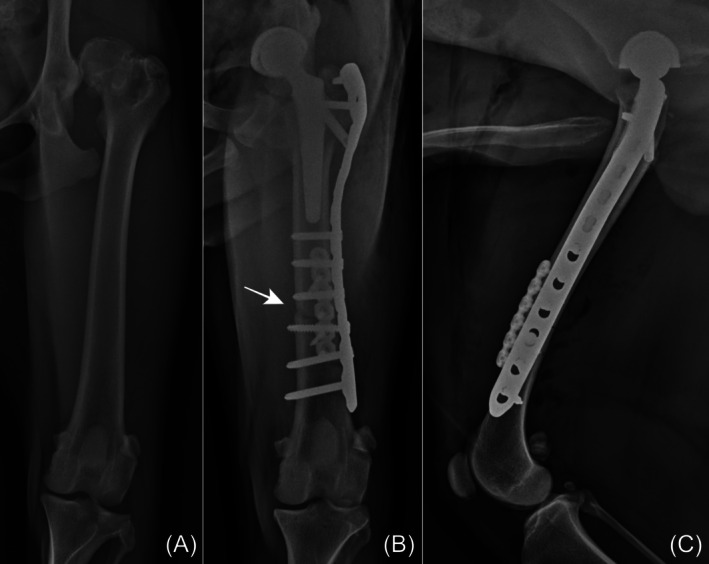

Methods: Standard THR was performed to alleviate pain and restore limb function. After confirming the prostheses were non-reducible, DFSO was performed as a novel tension-relieving technique at a level that allowed internal fixation. The shortening length was determined by the intraoperative tension required to reduce and maintain the prosthesis. Data from medical records were collected, including signalment, clinical signs, implant used, shortening length, and outcomes.

Results: Following DFSO, prosthesis reduction was successful in all dogs. The median femoral shortening length ratio was 13.8% (range, 10.7%-15.3%). One intraoperative complication involved a fissure of the greater trochanter, which occurred during trial reduction before DFSO. Median duration of follow-up was 21 months (range, 3-34 months). Two dogs showed good to excellent limb function. Bone union was consistently achieved in all DFSO procedures. Two postoperative complications were observed: one case of prosthesis luxation and one case of aseptic stem loosening. The owner declined revision surgery for luxation, and explantation was performed for the stem loosening.

Conclusion: DFSO could effectively manage irreducible prostheses in dogs with luxoid hips when conventional methods fail. However, careful case selection and meticulous surgical planning were essential to avoid complications.